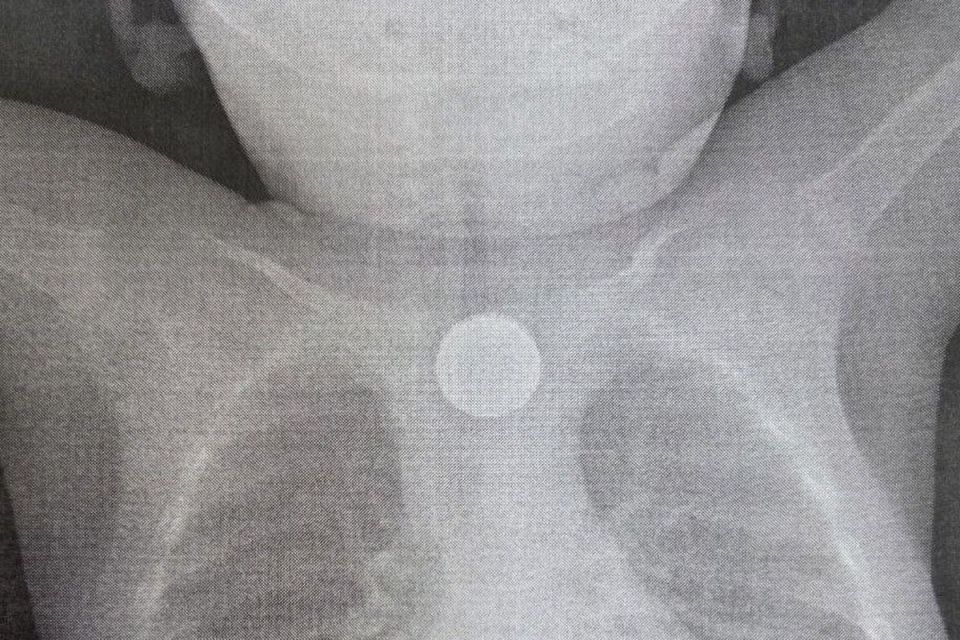

Срочная операция была проведена в Детской республиканской клинической больнице (ДРКБ) в Улан-Удэ, где медики спасли жизнь годовалому пациенту. Малыш проглотил дисковую литиевую батарейку и двухрублевую монету, что привело к тяжелейшему химическому...